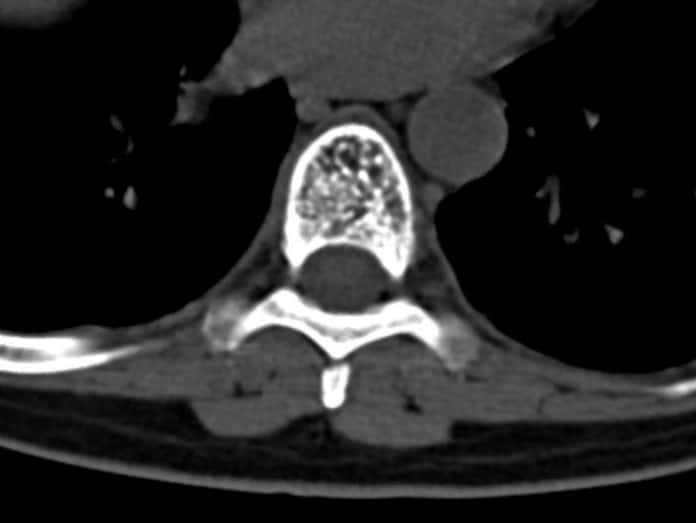

A vertebral hemangioma is type of benign spinal tumor. In adults, they are usually identified incidentally on CT or MRI.